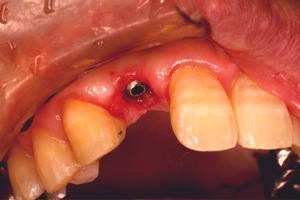

前歯即時埋入症例

主訴-前歯が腫れて痛い。治療法のうち、ブリッジとインプラントを説明して隣の前歯を削らないですむことからインプラントを選択された。

抜歯した穴をよく掃除(掻爬)後すぐにインプラントを埋入

二次オペ時